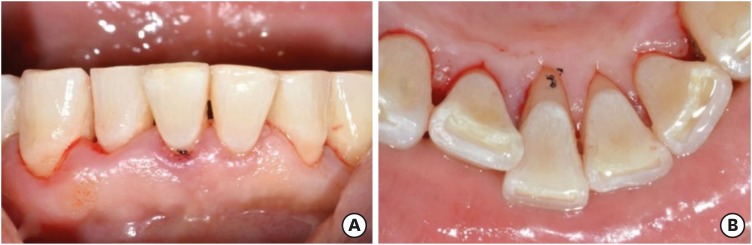

At a 10-month recall examination, the pontic and abutment teeth were in sound condition. No specific discomfort was reported, and the patient was satisfied with having saved his natural tooth. Periapical radiography was taken and it showed bony healing of the extraction socket (Figure 8).

Figure 8

At a 10-month recall check. (A) Intraoral photograph (labial view); (B) intraoral photograph (lingual view); (C) periapical view.

rde-45-e8-g008.jpg

The pontic and abutment teeth were in good condition at an 8-month recall examination. No specific discomfort was reported, although some calculus was present on the mandibular anterior tooth. Periapical radiography was taken and it showed bony healing of the extraction socket (Figure 13).

Figure 13

At an 8-month recall check.

rde-45-e8-g013.jpg